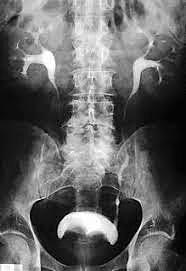

Primera Urografía con medio de Contraste en Francia

El doctor Gonzalo Esguerra viaja a Francia en noviembre de 1922, al Hospital de Vaugirar con el doctor Claude Beclere, donde asiste a la primera urografía en Francia con medio de contraste traído desde Alemania.